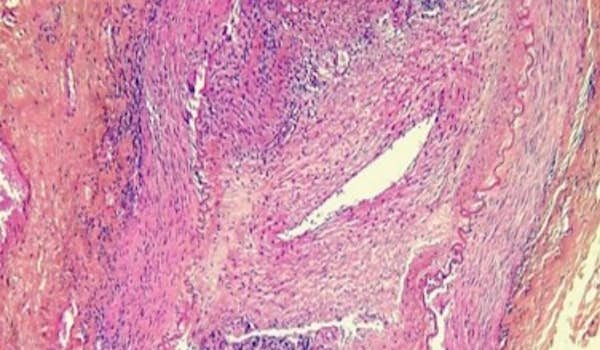

Artérite à cellules géantes (Horton)

C'est la vascularite la plus fréquente après l'âge de 50 ans. Cette vascularite, particulière par sa topographie, atteint préférentiellement les artères de gros et moyen calibre, principalement du territoire céphalique.